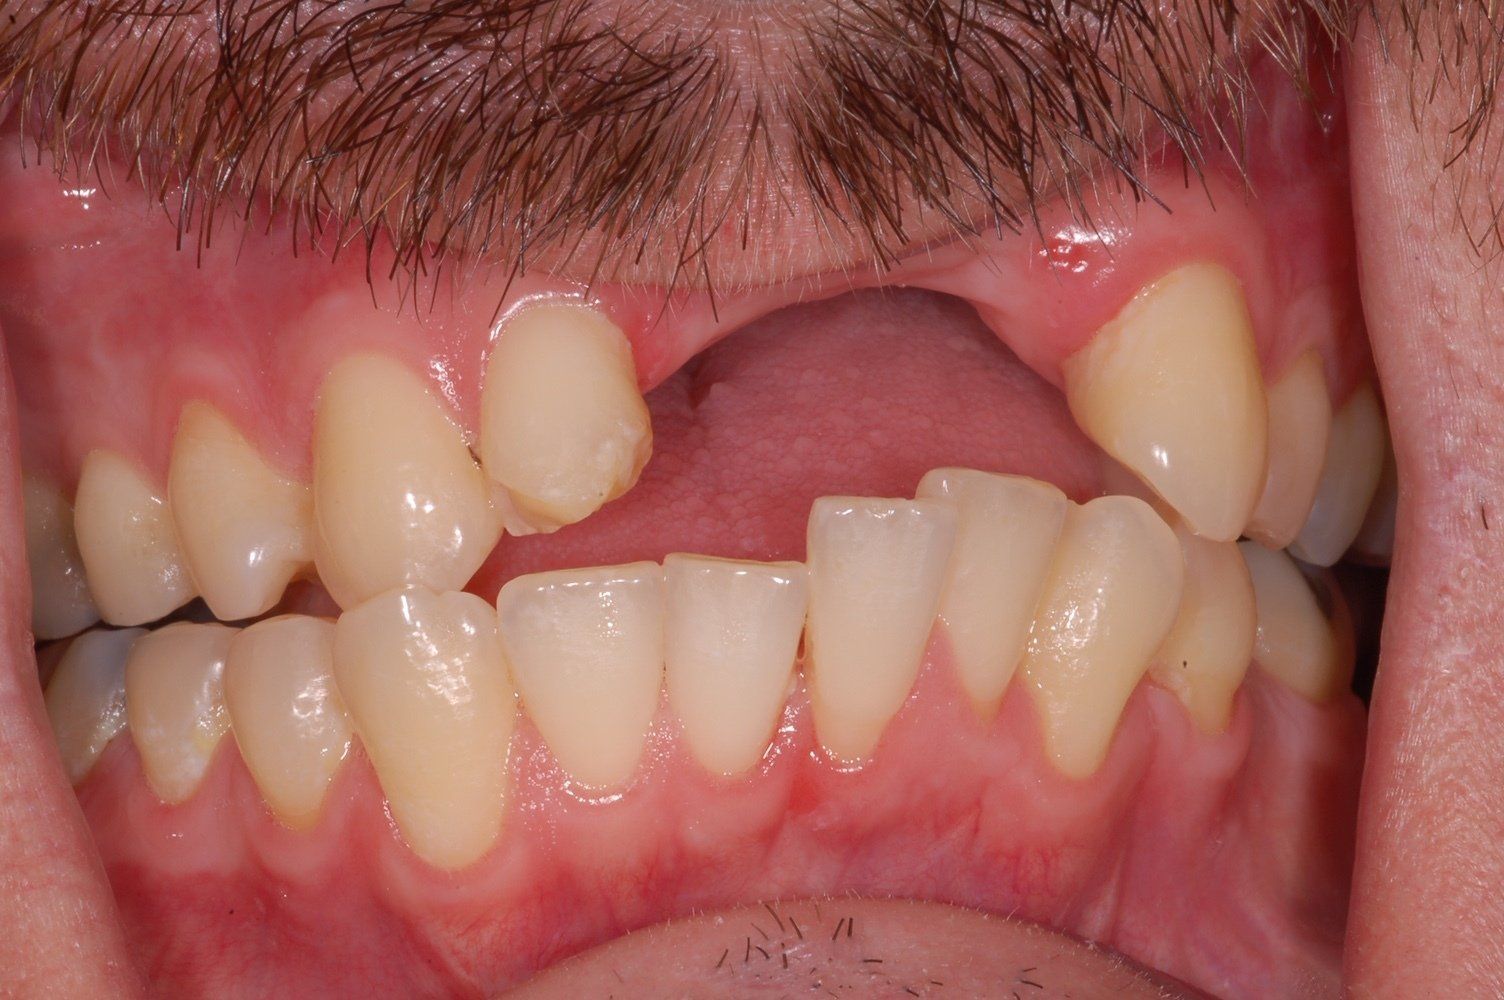

Single Porcelain Crown

Discoloured root canal treated tooth restored with a crown. You can hardly tell!